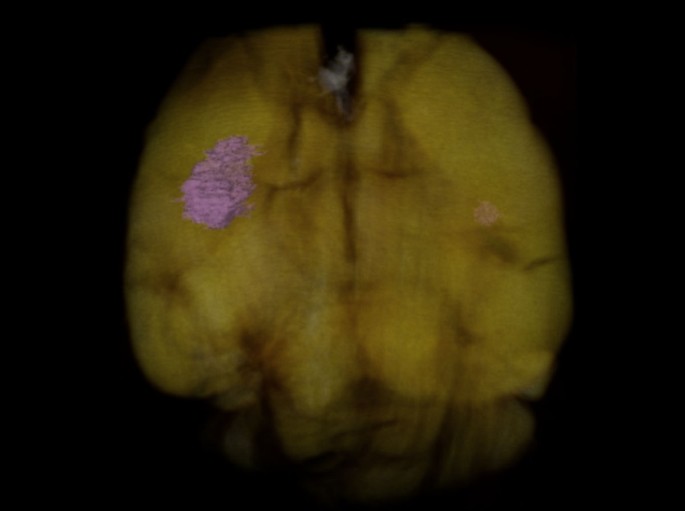

The full BMs were visible after the GPC-CT tomogram was reconstructed in three dimensions (see Fig. 4 and Supplementary Video S1).

The reconstructed mouse brain structure by GPC tomography.

Breast cancer metastatic foci in motor cortex and hippocampus are marked in pink.